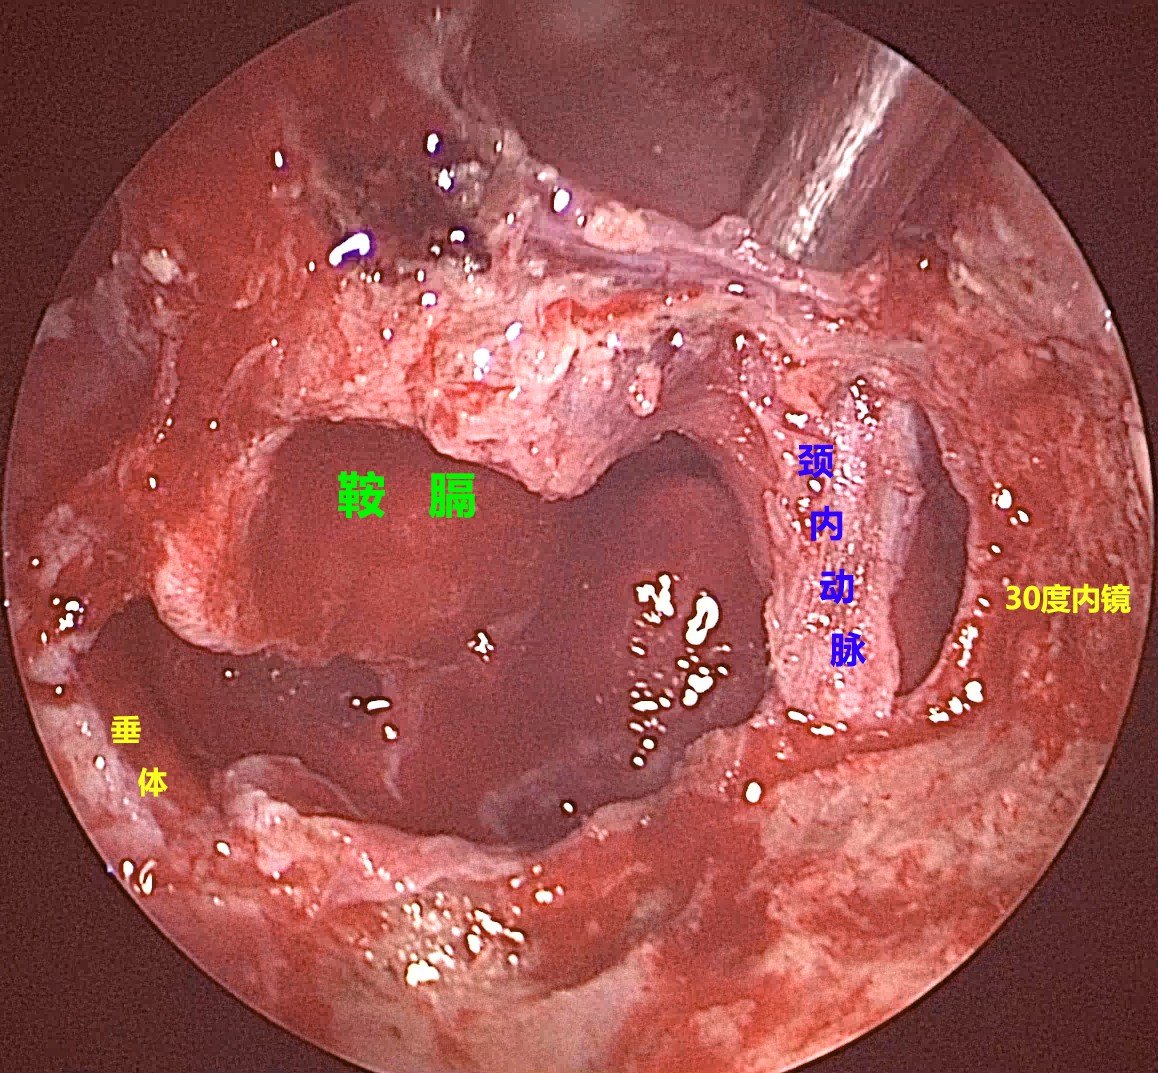

内镜下经鼻手术切除侵袭海绵窦的功能性垂体瘤

内镜经鼻切除垂体瘤相关技术小结游学意大利十三